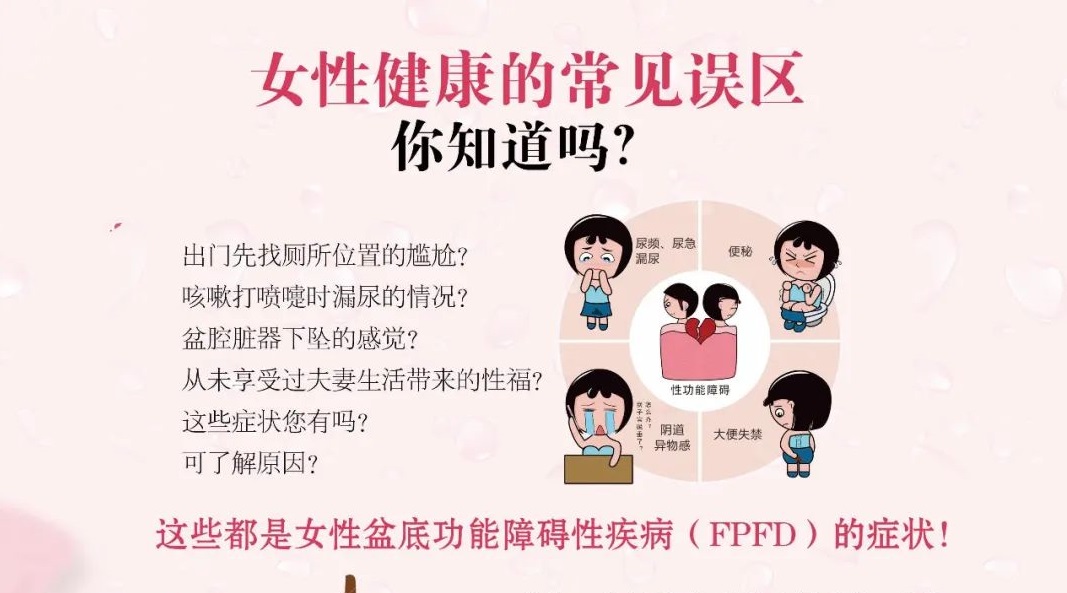

“医”万个为什么丨盆底康复检查,你做了吗?

很多人总以为 生完孩子的女性 恢复一段时间后就没问题了 但只有宝妈自己知道 身体大不如前 无论是剖宫产还是顺产 在生产过程中 很多妈妈的盆底都会 受到不同程度的损伤 比如 一出